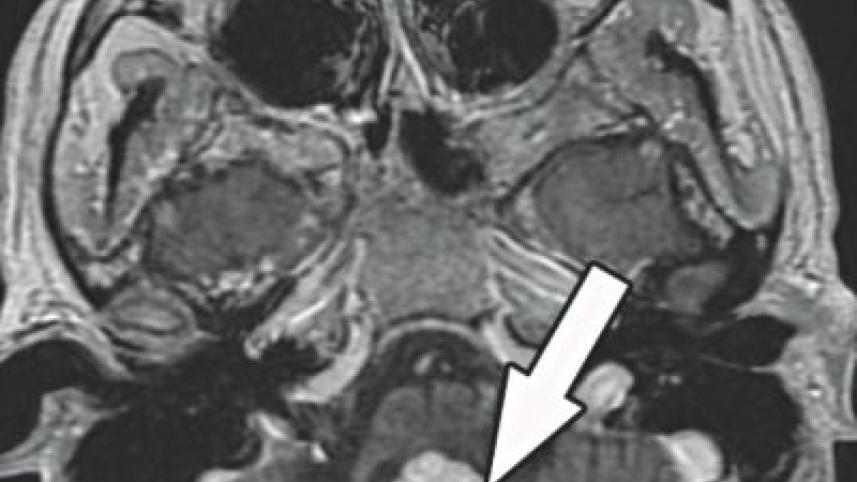

A Magnetic Resonance Imaging (MRI) scan of brain was done. It showed a tumour in the medulla, which is a part of brainstem. He started preparing for a medical consultation and was admitted in a nursing home. Very soon he became bedridden and he lost the ability to swallow food and even his saliva. A nasogastric tube was inserted to feed him. In just a matter of two months, he became completely bedridden from a fully active young man. The future was dark for the family.

The tumour was suspected to be a haemangioblastoma. Haemangio-blastomas are tumours of the central nervous system that originate from the vascular system usually during the middle age. Sometimes these tumours occur in other sites such as the spinal cord and retina. The tumours are extremely vascular, that means they bleed a lot during operation.

The operation was particularly risky and difficult as the tumour was inside the brainstem. The tumours touching or compressing the brainstem can be devastating. However, in this case you need to incise the brainstem, get inside and take the tumour out. A little bit of unsteady movement can put the patient in permanent coma or paralysis of all limbs, inability to swallow or even death.